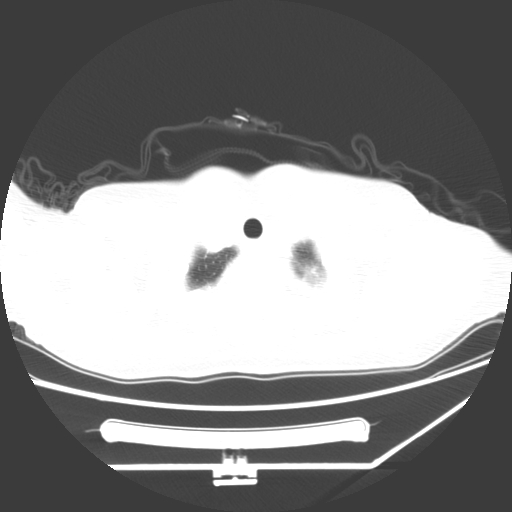

标题: CT25393:病人45岁,咳嗽,吐黄痰带血丝,发热,胸闷月余 [打印本页]

标题: CT25393:病人45岁,咳嗽,吐黄痰带血丝,发热,胸闷月余

1、左肺中央型肺癌并双肺弥漫性转移   2、双肺部感染    3、肺大泡     4、左侧胸腔积液

双侧肺弥漫性病变,可见“空泡征”及“蜂窝征”,考虑肺泡癌可能性大,左侧胸腔积液,考虑胸膜受累可能!

考虑肺泡癌,建议排除感染。

考虑肺泡癌

1)不排除肺泡癌可能。2)左侧胸腔积液。